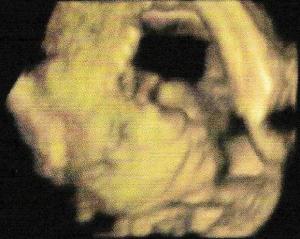

On en recommande 3 lors d’une grossesse, une à chaque trimestre. Ci-dessous quelques images d’échographie, tout d’abord le battement de son cœur et l’analyse du cœur ainsi que quelques prises de mesures qui aideront à définir la date prévue d’accouchement afin de faire la déclaration de grossesse : Image en 3D de la tête du bébé, lors de l’échographie du 2ème trimestre : echo3D_internet